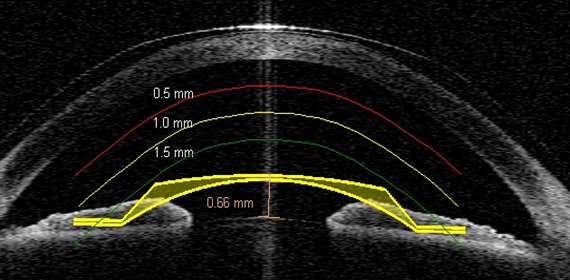

라식, 라섹 전/후 확인

수술 후 남아 있는 각막 두께, 라식 각막 절편(Flap) 두께, 엑스트라 수술/콜라겐 각막교차결합술 후 demarcation line 등을 볼 수 있는 안구 CT, 수술 결과를 평가하고 이상 유무를 확인할 수 있습니다.